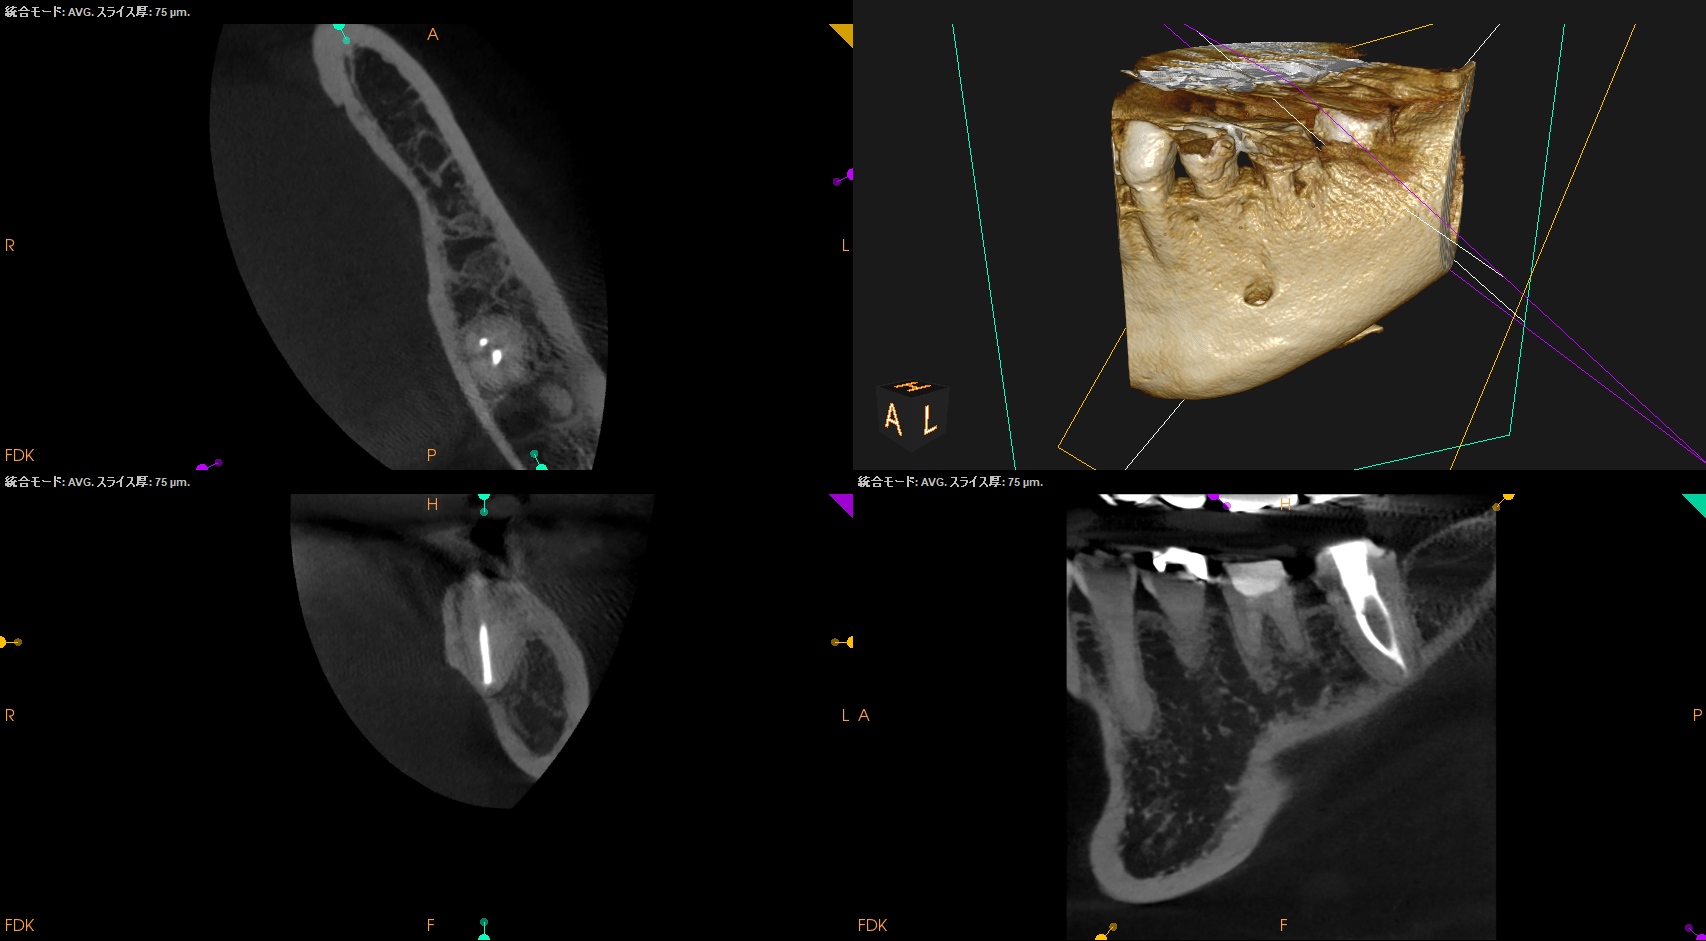

CBCTも撮影した。

CBCT(2025.10.31)

#19

MB

ML

D

ということで臨在歯の#18もCBCTを精査した。

#18

M

#18 Mのこの絵は縁下カリエスの可能性を示唆している。